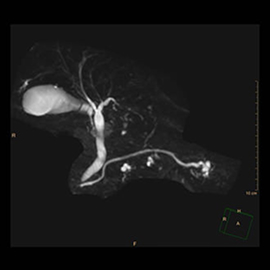

画像処理機能も従来装置に比べて大きく進化しており、患者さんの被ばくを低減しつつより高画質な画像が得られます。さらに、この装置ではAlphaCTと呼ばれる3D撮影により、高い濃度分解能を有したコーンビームCT画像の再構成が可能です。これにより、血管内治療に求められる画像を最適に表示します。

血管造影装置の検査画像例